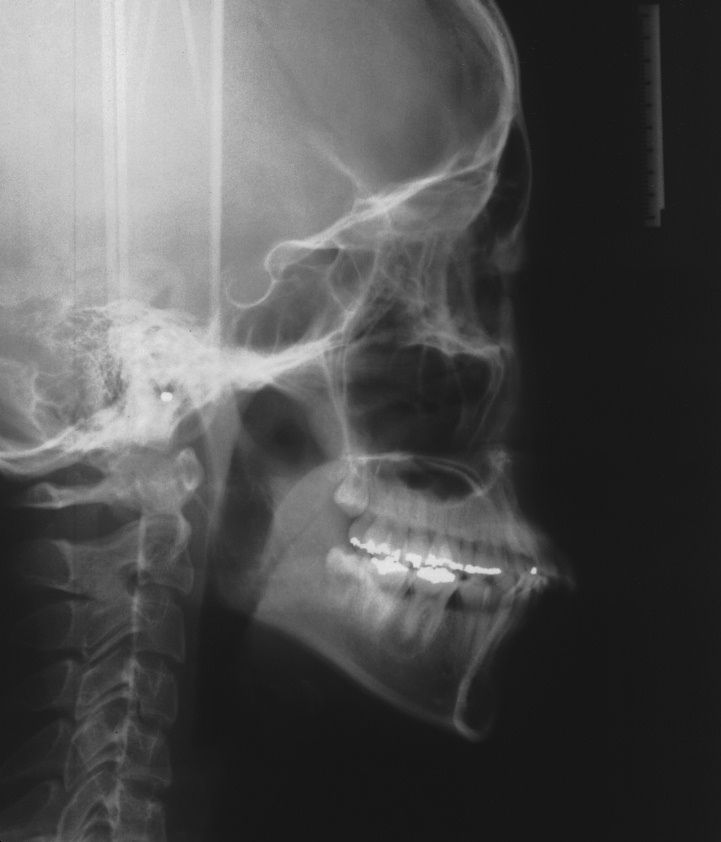

치료 전 사진입니다.